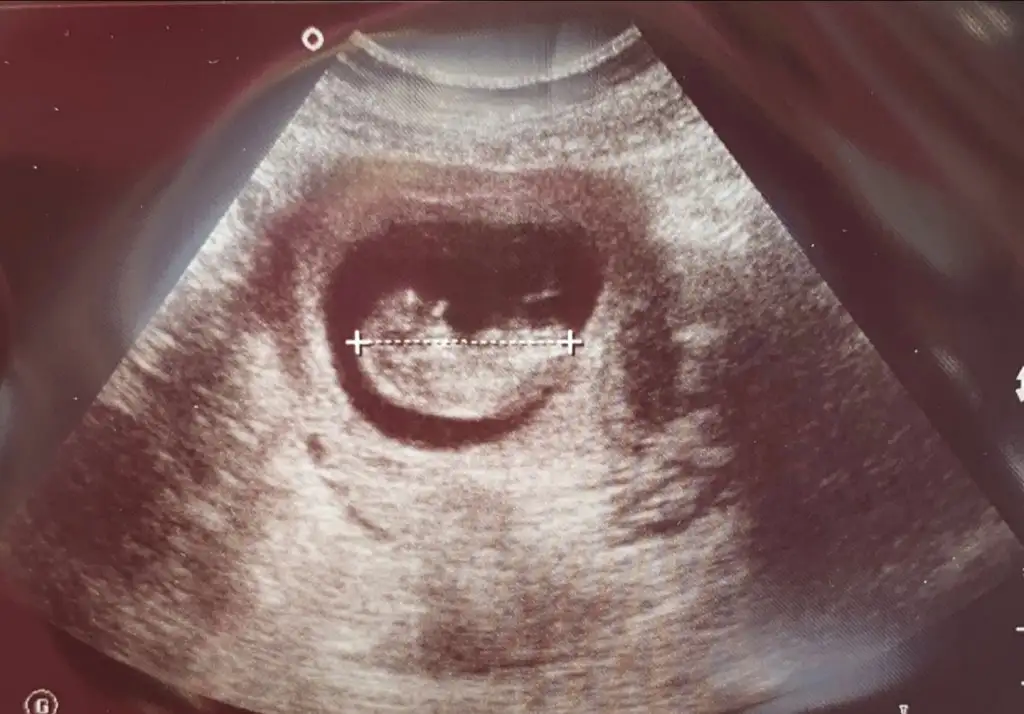

Burada 9+4 üz tahmin alabilir miyiz karından ultrason merak işte teşekkürler şimdidenErkek görünüyor![]()

Çok erken en iyi 11 12 13 haftalar olmalı şimdilik kız yönünde ama yanıltabilirBurada 9+4 üz tahmin alabilir miyiz karından ultrason merak işte teşekkürler şimdidenEki Görüntüle 2894467